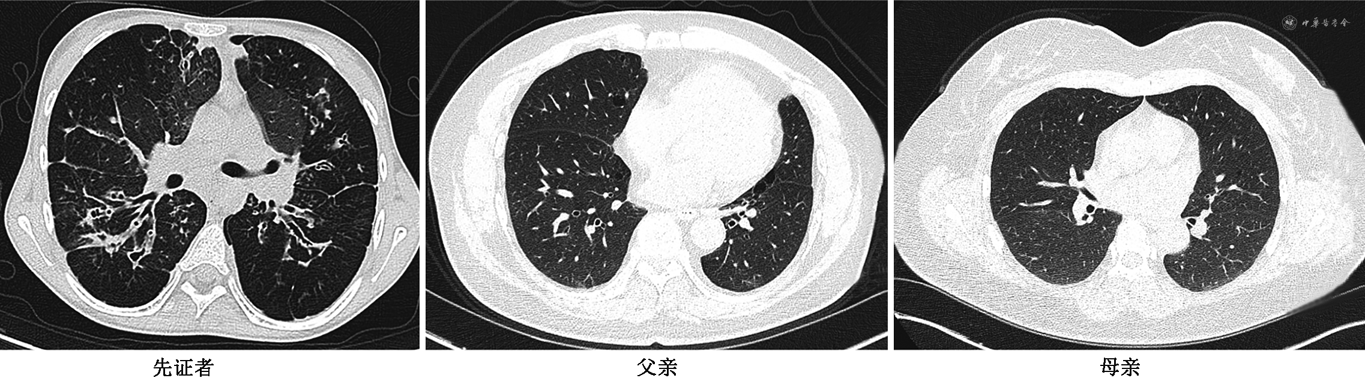

辅助检查:血常规示白细胞10.47×109/L[参考值(3.50~9.50)×109/L],单核细胞百分比2.3%(参考值3.0%~10.0%),中性粒细胞绝对值6.91×109/L[参考值(1.80~6.30)×109/L]。血沉108 mm/h(参考值0~20 mm/h),外周血涂片示中性粒细胞胞浆颗粒增多,部分成熟红细胞色素充盈欠佳。咽拭子培养阴性,痰培养鉴定为铜绿假单胞菌,超敏C反应蛋白112.4 mg/L(参考值<3 mg/L)。尿酸440 μmol/L(参考值142~416 μmol/L),免疫球蛋白G 24.06 g/L(参考值8.00~17.00 g/L),免疫球蛋白A 5.24 g/L(参考值0.72~4.92 g/L)。血脂:总胆固醇2.35 mmol/L(参考值2.83~5.17 mmol/L),甘油三酯1.87 mmol/L(参考值0~1.70 mmol/L),高密度脂蛋白胆固醇1.02 mmol/L(参考值1.15~1.94 mmol/L);糖化血红蛋白(glycated hemoglobin A1c,HbA1c)6.70%(参考值4.0%~6.0%);一步法口服75 g无水葡萄糖耐量试验结果示血糖:0 h 5.10 mmol/L,1 h 18.23 mmol/L(参考值6.00~11.10 mmol/L),2 h 14.88 mmol/L(参考值3.90~7.80 mmol/L),3 h 8.37 mmol/L(参考值3.90~6.10 mmol/L);C肽:0 h 1.21 ng/ml(参考值0.56~3.25 ng/ml),1 h 4.52 ng/ml,2 h 8.00 ng/ml,3 h 7.54 ng/ml。糖尿病相关抗体:胰岛素自身抗体阳性,胰岛细胞抗体、谷氨酸脱羧酶抗体、酪氨酸脱羧酶抗体均阴性。血酮体试验阴性,心肌酶谱正常,尿常规正常。CT示脾增大,左侧气胸,双肺多发斑片影,双肺支气管扩张伴感染(图1)。

家族史:先证者父亲,50岁,肥胖(体重指数29.5 kg/m2),患高血压20年,自述血压最高140/110 mmHg,口服替米沙坦(40 mg,1次/d)、氨氯地平(5 mg,1次/d)治疗;吸烟史30年,约每日1包,饮酒史20年,每个月2~3次,每次半斤白酒;本次检测FPG 7.47 mmol/L,空腹胰岛素210.50 pmol/L(参考值17.80~173.00 pmol/L),空腹C肽0.626 ng/ml;血清总胆固醇6.62 mmol/L,甘油三酯3.22 mmol/L;CT示双肺多发肺大疱(图1),同时报告显示双肺胸腔下轻度间质性改变,左下肺纤维灶,右肺下叶结节考虑肺内淋巴结、脂肪肝。先证者母亲,48岁,患糖尿病17年,目前口服二甲双胍片(0.5 g,3次/d),自述血糖控制较差;高血压10年,最高血压200/110 mmHg,平素口服苯磺酸氨氯地平片5 mg/d;高脂血症4年;20年前因急性化脓性梗阻性胆囊炎及胆囊结石行胆囊切除术;4年前因左侧肾上腺囊肿于泌尿外科手术治疗;7个月前发现甲状腺结节,未进一步诊疗;6个月前发生急性脑梗死于神经内科住院治疗,好转后出院;本次检测FPG 8.6 mmol/L,血脂正常;CT未见囊性纤维化相关表现(图1),报告左肺下叶钙化灶,主动脉钙化,左心增大,右侧乳腺结节,胆囊切除术后,肝脏边缘钙化灶。伯伯、姑姑体健;爷爷因肺气肿,呼吸衰竭去世;奶奶患高血压数年。外公因车祸去世;外婆患高血压18年、2型糖尿病13年、冠心病8年,具体治疗不详,家系统如图2。